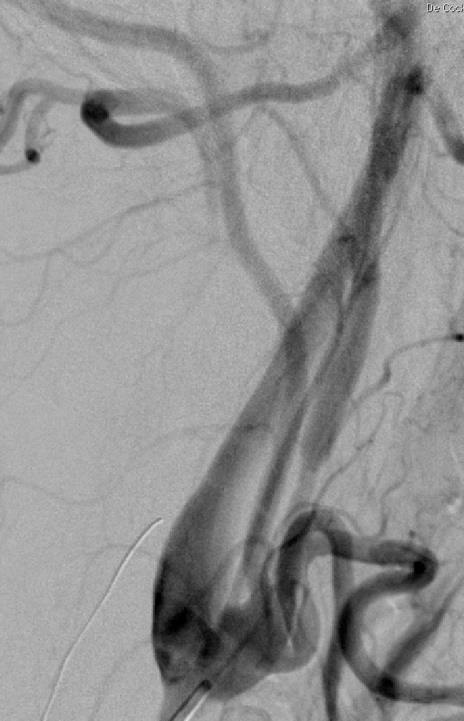

外伤后出血的栓塞

外伤后可见造影剂外溢 |

微导管选择至出血血管 |

出血血管的微弹簧栓子栓塞 |

栓塞后造影 |